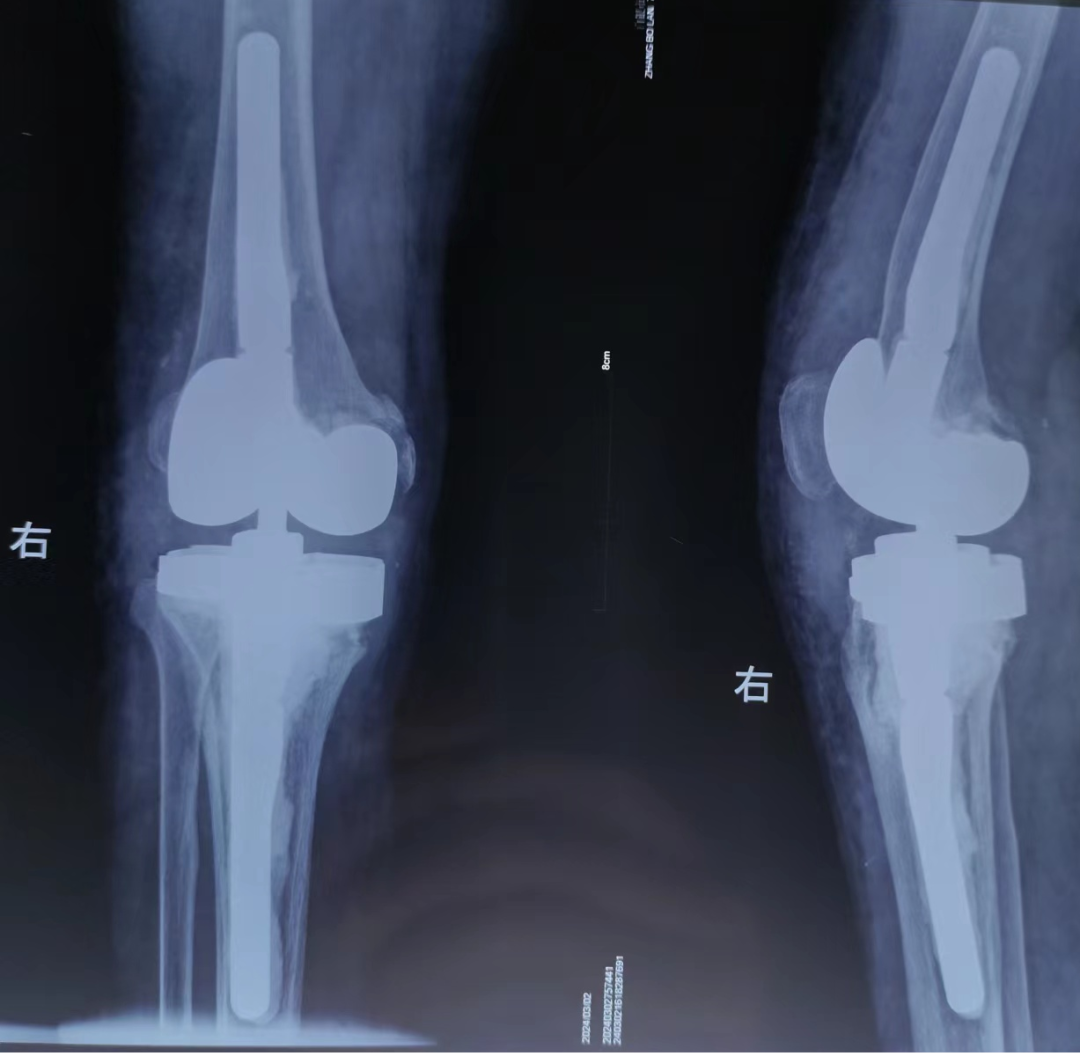

患者张某,女,71岁,因“右膝关节反复肿胀疼痛伴活动受限半年余”来我院,询问病史得知于2012年行右膝关节置换手术,复查膝关节DR片提示:右侧膝关节置换术后假体松动,半年来右膝关节病情已严重影响日常生活,患者及家属手术意愿强烈。入住后朱雄主任医师高度重视,经认真研究讨论病情,最终决定为患者行右膝LCCK翻修手术,手术难点在于重建胫骨骨缺损、纠正软组织失衡,以最小限制性达到最大关节稳定性,同时还要控制翻修手术的高感染率难题。

经过精心术前准备,2月28日成功为患者实施了手术。手术历时2小时30分钟,术后制定了详细的康复计划,科室护理团队悉心指导锻炼,术后5日便能辅助下床行走,手术切口也愈合良好,患者及家属对手术效果十分满意,由衷地表示感谢!